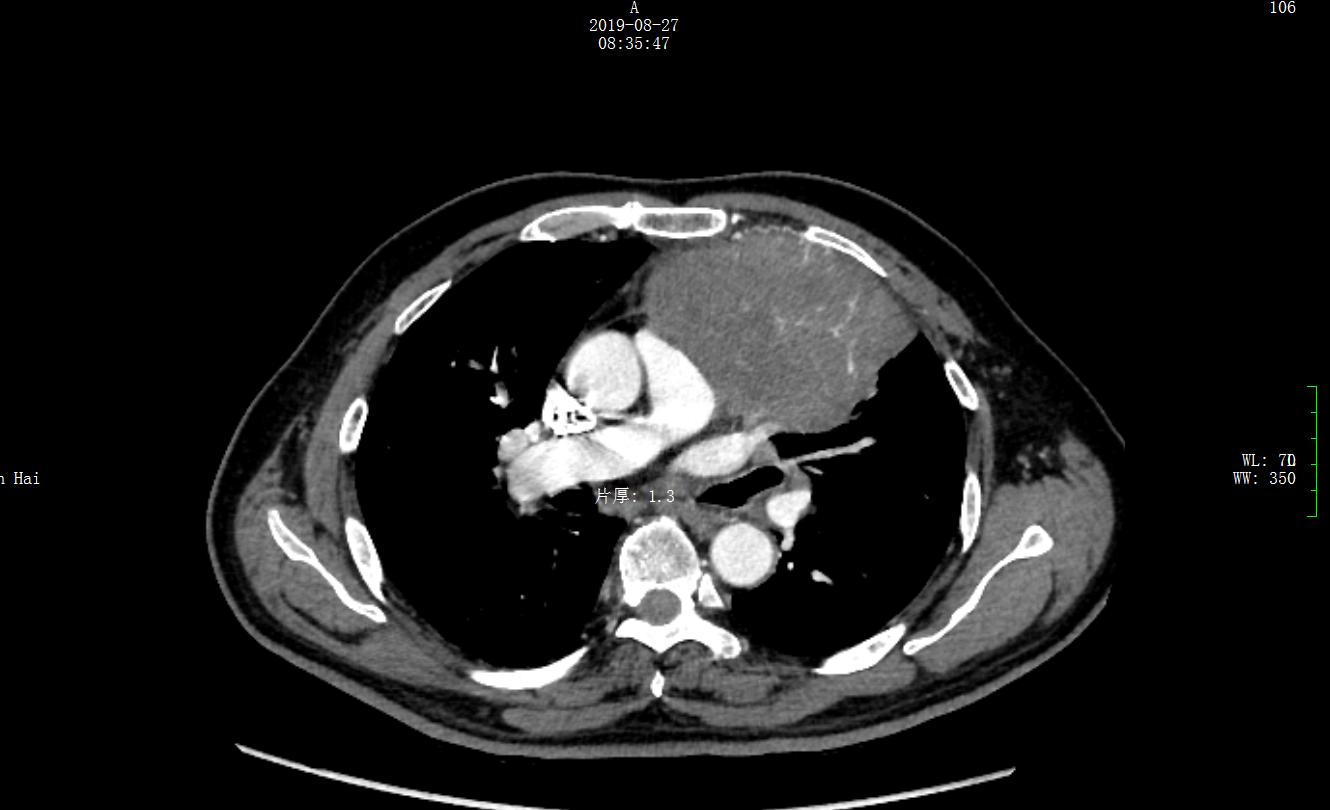

入院后胸部CT平扫+增强病灶